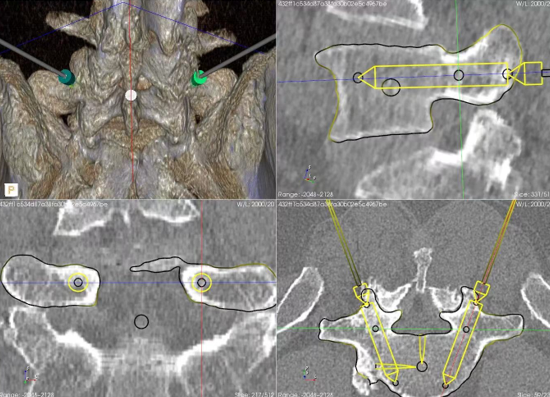

手术台上,在完成前路前方OLIF融合术后,还需进行后路腰4/5椎弓根螺钉固定,在脊柱机器人引导下,每个椎弓根螺钉仅花费2分钟左右便完成了导针精准植入,比传统C臂机反复定位下的植入时间大大减少。

钱宇教授介绍,OLIF手术已经在浙江省中医院常规开展。脊柱手术机器人可以通过术前规划,精准模拟术中各种内植物的置入轨迹,在经皮椎弓根螺钉植入、椎间孔镜手术定位穿刺、经皮球囊扩张手术穿刺等操作中提供实时引导,尤其在风险更高的胸椎或脊柱畸形等手术中,缩短手术时间。两种微创技术的融合,避免原本需要大切口的传统手术方式。